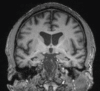

Neurodegenerative diseases are a devastating group of disorders that can be difficult to accurately diagnose. Although these disorders are difficult to manage owing to relatively limited treatment options, an early and correct diagnosis can help with managing symptoms and coping with the later stages of these disease processes. Both anatomic structural imaging and physiologic molecular imaging have evolved to a state in which these neurodegenerative processes can be identified relatively early with high accuracy. To determine the underlying disease, the radiologist should understand the different distributions and pathophysiologic processes involved. High-spatial-resolution MRI allows detection of subtle morphologic changes, as well as potential complications and alternate diagnoses, while molecular imaging allows visualization of altered function or abnormal increased or decreased concentration of disease-specific markers. These methodologies are complementary. Appropriate workup and interpretation of diagnostic studies require an integrated, multimodality, multidisciplinary approach. This article reviews the protocols and findings at MRI and nuclear medicine imaging, including with the use of flurodeoxyglucose, amyloid tracers, and dopaminergic transporter imaging (ioflupane). The pathophysiology of some of the major neurodegenerative processes and their clinical presentations are also reviewed; this information is critical to understand how these imaging modalities work, and it aids in the integration of clinical data to help synthesize a final diagnosis. Radiologists and nuclear medicine physicians aiming to include the evaluation of neurodegenerative diseases in their practice should be aware of and familiar with the multiple imaging modalities available and how using these modalities is essential in the multidisciplinary management of patients with neurodegenerative diseases.©RSNA, 2020.